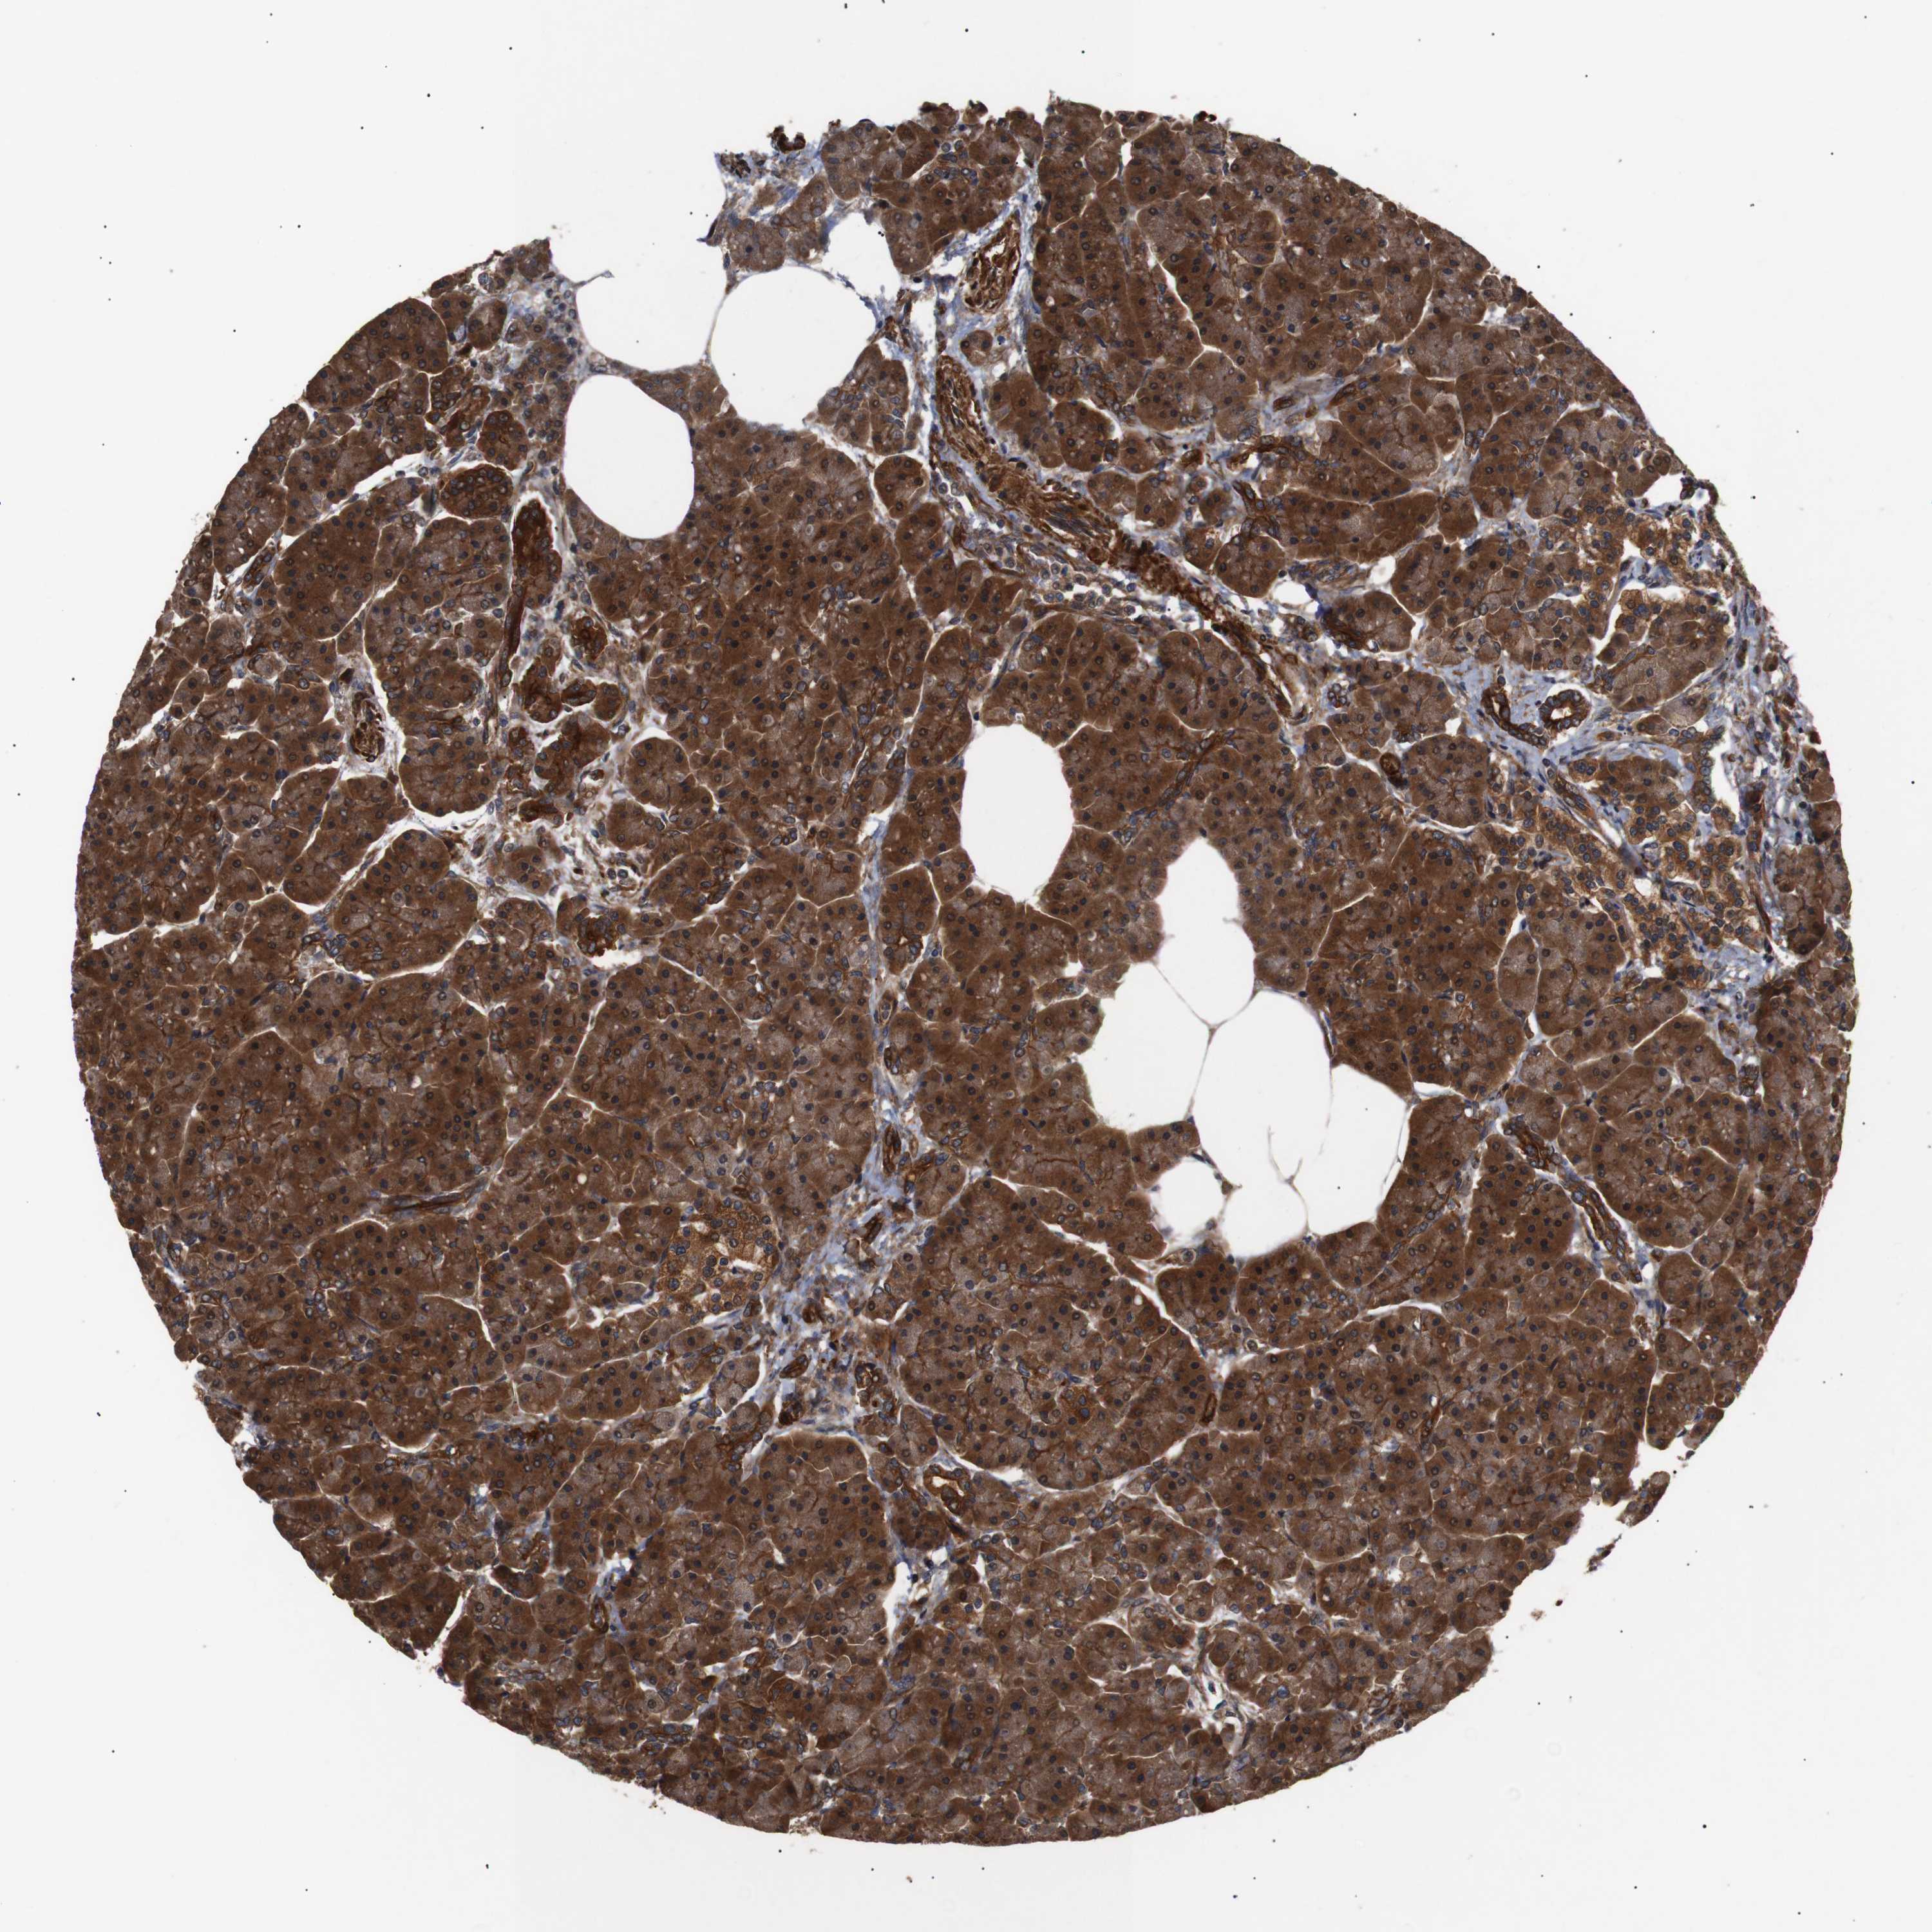

PANCREAS - Antibody stainingi

Antibody staining in the annotated cell types in the current human tissue is reported as not detected, low, medium, or high, based on conventional immunohistochemistry profiling in selected tissues. This score is based on the combination of the staining intensity and fraction of stained cells.

Each image is clickable and will lead to virtual microscopy that enables deeper exploration of all samples and also displays staining intensity scores, fraction scores and subcellular localization as well as patient and tissue information for each sample.

Antibody HPA012640Antibody CAB020779

Exocrine glandular cells HighLow

Pancreatic endocrine cells HighNot detected